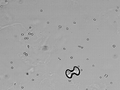

Urine microscopy showing a calcium oxalate monohydrate crystal (dumbbell shaped) and a calcium oxalate dihydrate crystal (envelope shaped) along with several erythrocytes.

Urine microscopy showing several calcium oxalate monohydrate crystals (dumbbell shaped, some of them clumped) and a calcium oxalate dihydrate crystal (envelope shaped) along with several erythrocytes.